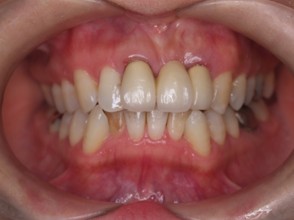

矯正治療・根管治療・補綴治療の症例紹介(三隅歯科クリニック)

| 主訴 | 過去作成した右下の被せ物がずれて入っており、たまに腫れる。歯並びも気になる。 |

| 治療内容 | 矯正治療を行いました。 |

| 治療費 | 800,000円(税込み) |

| 治療期間 | 2年半(矯正治療期間 2年) |

| 治療回数 | 30回 |

| 想定されたリスク | 術前に基礎資料を整え分析し、セットアップモデル等でシミュレーションをしておかないと、予定通りの治療が行えないリスクがあった。 |